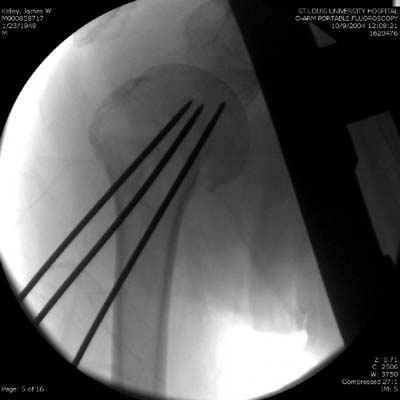

Здравствуй Женя. Во первых спицы, вводимые в головку плеча ретроградно, никогда не имели V-образную форму, если говорить о методике моей операции ЦИТО. Чтобы легче было запомнить Y-образную форму, вспомни крепление новогодних елочных шаров - очень демонстративно. Кроме того если ты внимательно посмотришь, то увидишь, что вся конструкция имеет некоторую кривизну по плокскости, величину, которой ты можешь задать сам. Сначала мы проводим проксимальный пучок, а в момент пересечения линии перелома мы

ротируем спицу таким образом, чтобы дистальный изгиб прямо противодействовал смещающим силам - поврот за ушко под контролем ЭОПа. Дистальный пучок стараемся провести так, чтобы его бранши расклинились и прошли по обе стороны предыдущего пучка, что создает дополнительное напряжение на

протяжении контакта. Для оценки правильности проведения спиц очень важно, чтобы ЭОП стоял строго перпендикулярно плоскости сустава, в противном случае - в рентгене есть эффект отбрасывания тени - прохождение косого луча дает удлиненное изображение спиыц и создается впечатление, что спица стоит уже в субхондральном слое. На первых операциях у нас было довольно частое несовпадение длины контрольной спицы и мы провизорно добавляли от 0,5 до 1,0 см уже на фиксирующем пучке. Входные отверстия лучше располагать по наружной и передней поверхности плеча на расстоянии не менее 2-х диаметров головки.

Такой выбор входных отверстий обусловлен прямой возможностью попадания в малый и большой бугорки за счет изгиба спиц по длине и отражения из от внутреннего кортикала проксимальнее точки введения. Поскольку анатомически бугорки не составляют артикулирующую поверхность, то некоторое выстояние спиц только усилит стабильность. Входное отверстие мы используем 6 мм в диаметре, для эффективного раскрытия петли-пружины. Спицы перед проведением

проверяем на достаточную эластичность и упругоустойчивость, мягкие спицы отбраковываем. В данном примере создалось впечатление, что одна бранша V-спицы скользнула по картикалу снаружи? Все это безболезненно можно переделать, расширив теже отверстия, изогнув спицы, повернув их в разные стороны и добавив еще пучки Y-ОБРАЗНЫХ, а не V-образных (эти пучки выталкивает, особенно если они прямые - пружина работает в обе стороны).